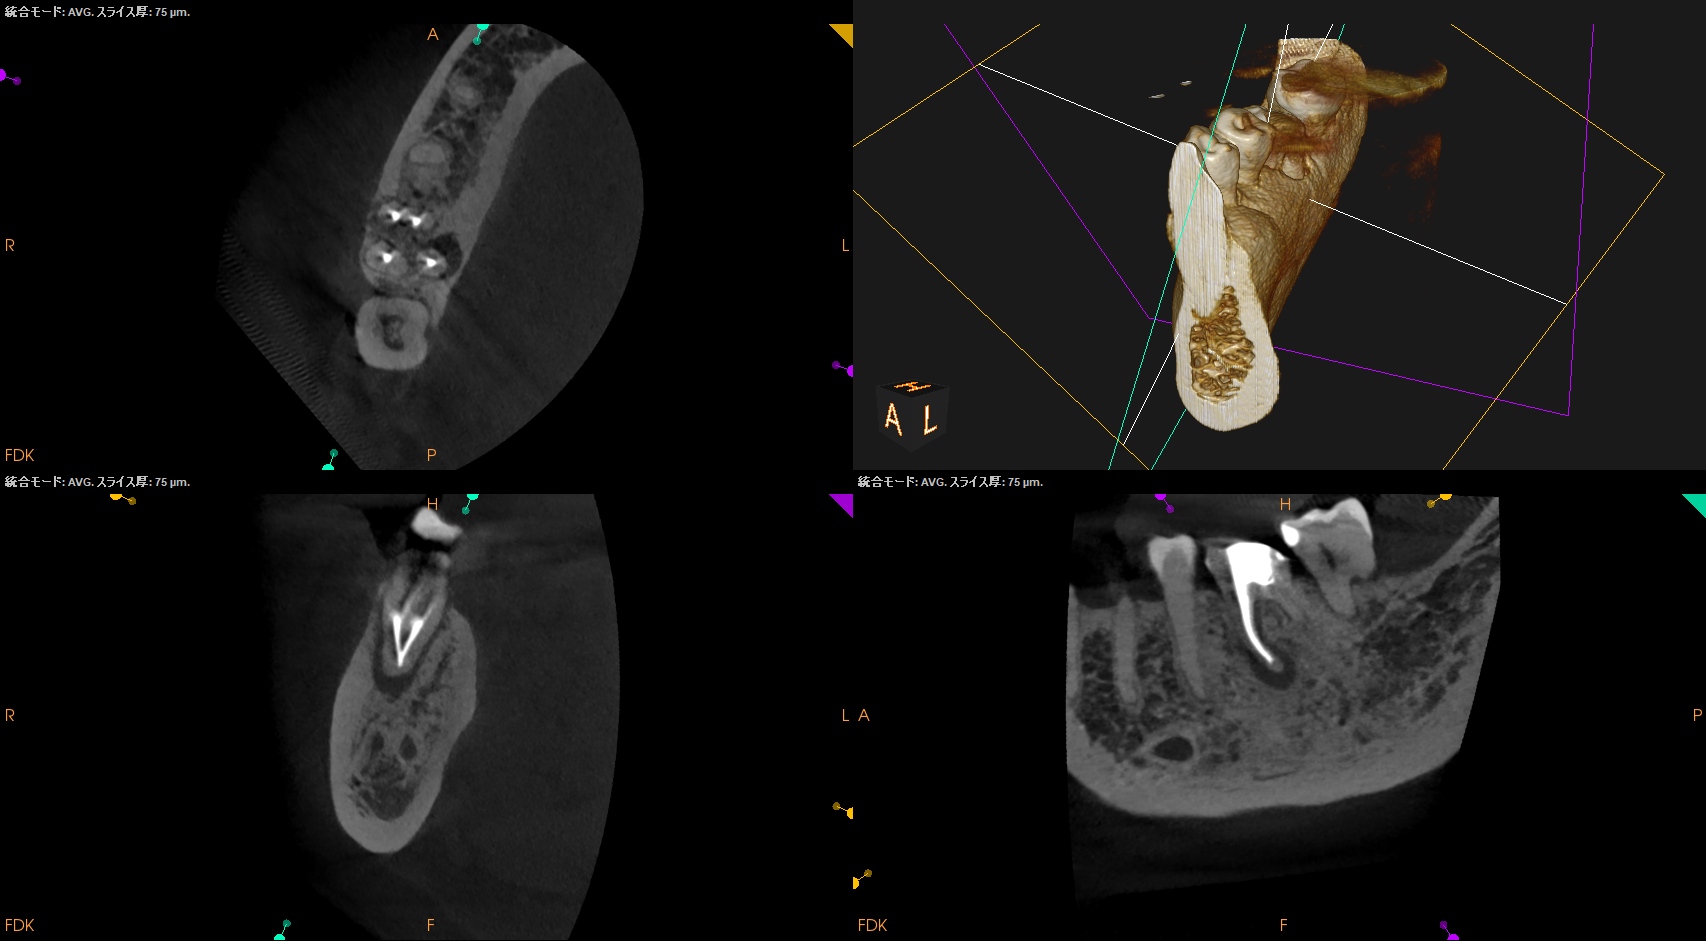

そこそこ湾曲度合いが強いRadix Entomolarisを有する#30だ。

が、D以外の根管はほぼ適切な根管治療がなされていない。

Radixにおいては未着手だ。

支台築造後にPA, CBCTを撮影した。

MB

ML

D

Radix

問題はないだろう。